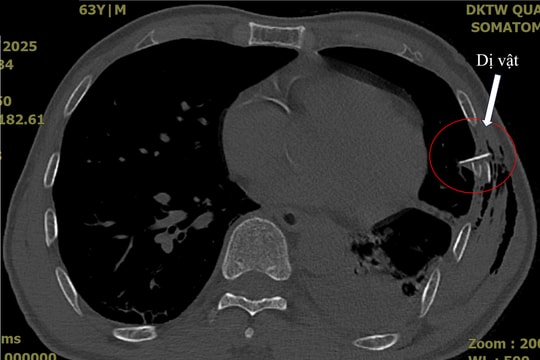

Bệnh viện Đa khoa Trung ương Quảng Nam điều trị thành công ca tràn khí màng phổi phức tạp

ĐNO - Bệnh viện Đa khoa Trung ương Quảng Nam vừa điều trị thành công một trường hợp tràn khí màng phổi phức tạp do kén khí vỡ.